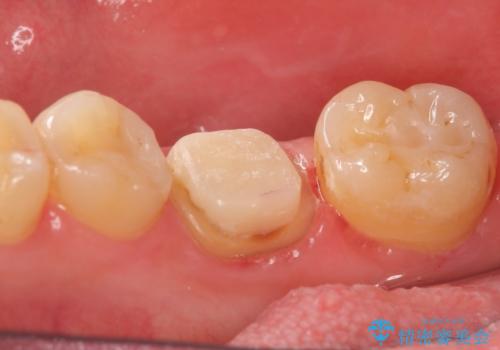

- 右下の奥歯の鈍い痛みがずっと続いているので診て欲しいといらっしゃった方の症例です。

検査の結果右下6に根尖病変を認めたため、再根管治療を行いました。

その後症状の消失を確認し、オールセラミッククラウンによる補綴を行いました。